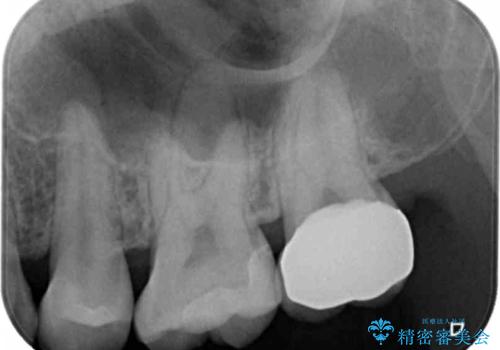

初めは一番奥の歯の樹脂の詰め物のやり替えをする予定でしたが、予想よりも歯の厚みが取れなかったため破折リスクを抑えることを目的にクラウンで修復処置を行いました。

その際手前の歯にも虫歯が確認されたため、こちらはインレーでの修復処置を行いました。

詰め物の除去をした結果、残った歯が少ないと今後の破折リスクを考慮しクラウンをおすすめすることがあります。